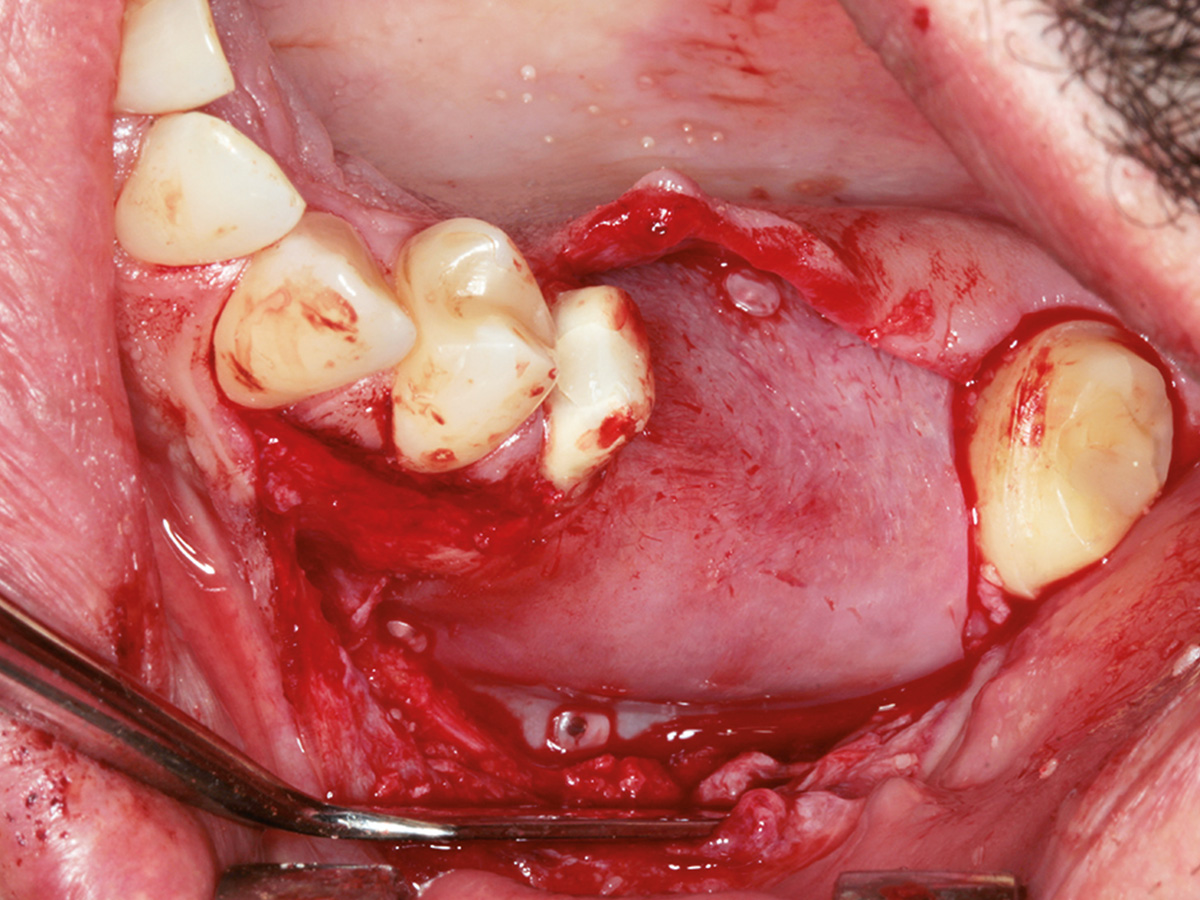

Osseodensifikation ist eine einfach zu erlernende Technik, die hilft, das Implantatlager zu verbessern. Besonders imOberkiefer, wo weicher Knochen häufig keine ausreichende Primärstabilität bietet, können mithilfe der Densah-Bohrer Verbesserungen erzielt werden, um eine reizfreie Einheilung derImplantate zu gewährleisten. Die aber wohl bemerkenswerteste Eigenschaft der Spezialbohrer ist, dass sich damit absolutminimalinvasive geschlossene Sinusaugmentationen durchführen lassen, was für Patienten sehr angenehm ist. Trotz technischer Innovationen muss in vielen Fällen zusätzlich augmentiert werden. Auch hier kommt den Materialien eine ganz besondere Bedeutung zu. Wird partikulär mit Knochenersatzmaterial augmentiert, müssen Membranen verwendet werden. Unzählige aufdem Markt befindliche Produkte haben sehr unterschiedliche Indikationsbereiche und variieren stark in Ergebnis und Handling.

In diesem Kurs wird das Handling mit der Bone Lamina samt Augmentation geübt. Danach sollte jeder Teilnehmer inder Lage sein, im Praxisalltag Knochen aufzubauen. Dazu isteine korrekte Schnittführung notwendig, die ebenfalls thematisiert wird. Damit ein Knochenaufbau erfolgreich einheilt, ist der spannungsfreie Wundverschluss zwingend erforderlich.Deshalb wird im Kurs auch besonderes Augenmerk auf spezielle Nahttechniken gelegt, die am Modell und am Schweinekiefer geübt werden.